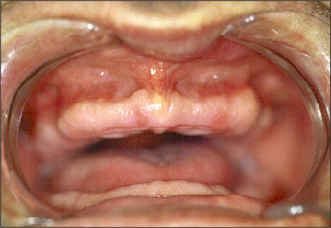

Excision of a maxillary or mandibular torus

A torus (Figs 11.13, 11.14) is a developmental bone exostosis, present typically either on the midline of the hard palate or on the lingual aspect of the mandible above the mylohyoid ridge (usually bilat-erally). Patients are often unaware of their existence. There are other causes of bony expansion of the jaws, some of which may have a history of slow onset and gradual enlargement. A neoplastic lesion (usually of minor salivary gland origin) sometimes develops on the hard palate, and it has been known for a dentist to ease a denture to accommodate an enlarging malignant growth. If there is doubt about the nature of any lesion, the patient is referred for a specialist opinion.

Fig. 11.14 Torus palatinus is typically symmetrical about the midline of the hard palate.